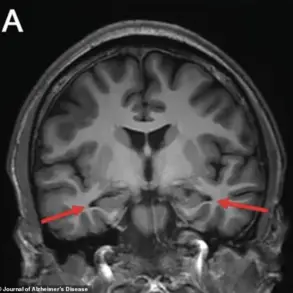

A single gene could be responsible for more than 90 per cent of Alzheimer’sdisease cases, new research suggests – a finding that could open the door to a new generation of treatments targeting the condition at its genetic roots

Alzheimer’s, the most common form of dementia, affects around 982,000 people in the UK, with early symptoms including memory loss, cognitive decline, and language difficulties.